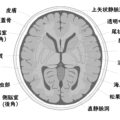

以前にも紹介しましたが、古代のインドで使われていた言語「サンスクリット語」でマントラ(日本語では真言とも言われ、神秘的な力を持つとされる語句)を記憶して暗誦すると、脳の灰白質が増加する――そんな調査結果が明らかになったという記事が、Newsweek日本版に記事が載っていました。